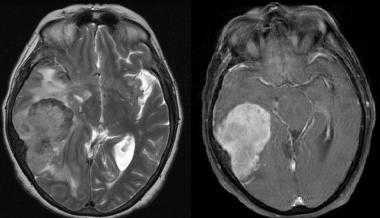

Метастазы головного мозга на МРТ. Фото. Определяются множественные метастазы в мозг при раке легкого: слева в режиме Т1-ВИ в виде гипоинтенсивных образований, справа — в режиме Т2-ВИ виде множественных участков повышенного сигнала, окруженных зоной перифокального отека. У пациента подтверждена первичная опухоль легкого.

Отдельно необходимо рассмотреть МР-признаки метастазов меланомы в головной мозг, которые обладают сигнальными характеристиками, отличающимися от других опухолей вследствие наличия меланина в структуре. Метастазы безамилоидной меланомы выглядят на МРТ аналогично метастазам других опухолей, описанным выше. На Т1-ВИ они имеют резко гиперинтенсивный (высокий, яркий) сигнал, а наТ2-ВИ — изо- либо гипоинтенсивный (пониженный) сигнал.

Признаки метастазов мозга на МРТ

- Объемные образования имеют гипоинтенсивный по отношению к серому веществу (СВ) сигнал.

- Геморрагический компонент с соответствующими сигнальными характеристиками.

- Гиперинтенсивное утолщение.

- Гиперинтенсивный вазогенный отек.

- Может наблюдаться ограничение диффузии в области МПТМО.

- Накапливающие контраст двояковыпуклые образования, смещающие головной мозг.

- Инвазия в нижележащую мозговую ткань